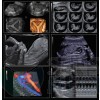

Ultrasonograf GE Voluson E6 wersja oprogramowania BT13 (UISApp 13.0.6.254) 4D HDLive –

rekondycjonowany 2019

System Voluson E6 to unikalne rozwiązanie w zakresie diagnostyki chorób kobiecych oferujące wysoką jakość obrazowania w trybach 2D i 3D/4D oraz uproszczone procedury usprawniające przepływ pracy i zapewniające najwyższą jakość badań. Więcej szczegółów, mniej wysiłku!

Oprócz najnowocześniejszych opcji obrazowania w usg 2D 3D 4D oraz opcji dopplerowskich posiada także funkcję ELASTOGRAFII.